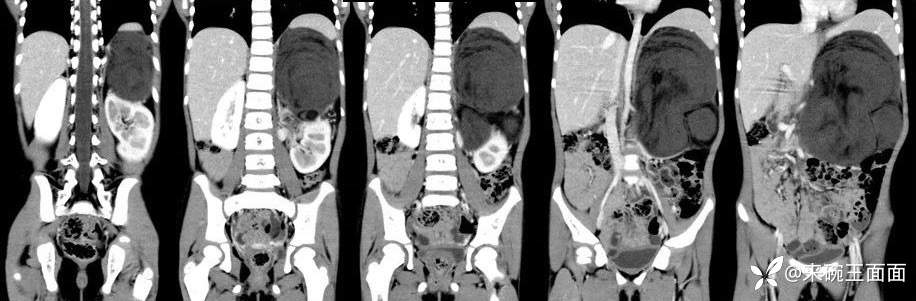

[现病史]1月余前无明显诱因发现左上腹肿物,无发热,无呕吐,无腹痛、腹泻、排便困难及其他不适,无尿频尿急,至当地医院CT示左上腹巨大占位性病变。【体格检查]腹膨隆,未及胃肠型及蠕动波,未及腹壁静脉曲张,腹软,左上腹可及大小约10*10cm肿物,质中,位置固定,无压痛、反跳痛,肝脾肋下未及,移动性浊音阴性,肠鸣音4-5次/分。

左上腹巨大软组织肿块影,密度混杂,边界清楚,其内可见脂肪密度,增强扫描未见强化。